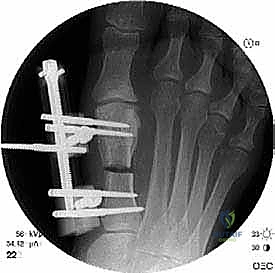

الخطوة الخامسة: التثبيت الداخلي القوي (Internal Fixation)

لضمان التئام العظم في وضعه الجديد والطويل، يجب تثبيته بقوة شديدة. يستخدم الدكتور هطيف أحدث الشرائح المعدنية التيتانيوم ذات الزاوية الثابتة (Locking Plates) والمسامير الدقيقة. هذا التثبيت القوي يمنع أي حركة بين العظام ويسمح ببدء العلاج الطبيعي في وقت مبكر.

الخطوة السادسة: الإغلاق التجميلي

بعد التأكد من الطول المثالي واستقرار التثبيت باستخدام الأشعة السينية في غرفة العمليات، يتم غسل الجرح بمضادات حيوية وإغلاق طبقات الأنسجة والجلد بخياطة تجميلية دقيقة لتقليل الندبات قدر الإمكان. يتم وضع ضمادة ضاغطة وداعمة للقدم.